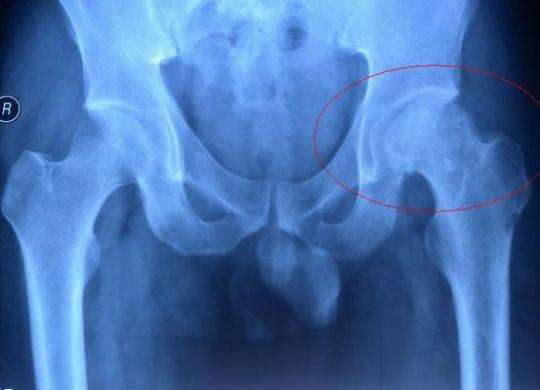

成人先天性髖關(guān)節(jié)脫位,也稱(chēng)為成人髖臼發(fā)育不良,是一種先天性的發(fā)育異常,是引起髖關(guān)節(jié)疼痛的常見(jiàn)原因之一,也是髖關(guān)節(jié)骨性關(guān)節(jié)炎的重要致病因素。一般認(rèn)為該病在女性的發(fā)病率要高于男性,男女比例約為1:5,并且在1/4的患者中存在家族史。在正常的髖關(guān)節(jié),碗狀的髖臼對(duì)球形的股骨頭覆蓋良好,髖臼和股骨頭之間還有一些軟骨和關(guān)節(jié)囊起到穩(wěn)定的作用。當(dāng)髖臼發(fā)育不良時(shí),髖臼碗變淺并且向外翻轉(zhuǎn),導(dǎo)致它對(duì)股骨頭的包容性變差,股骨頭容易向外上方移位,發(fā)生半脫位。